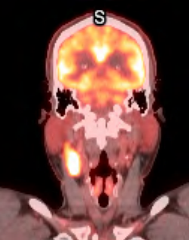

This patient

View attachment 395829View attachment 395830

presented with a 4.5 cm right level 2 node, p16+. On resection and search for primary all that was found was a single 4.5 cm node with ENE. Wondering who would do unilateral RT.

With ENE would treat CL neck. Could just do level 2 +/- 3.This patient